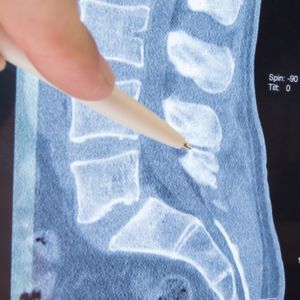

A herniated disc occurs when the outer annulus weakens, cracks, or tears — allowing the inner nucleus to push against the outer wall, bulge beyond it, or extrude through it entirely. When the herniated material contacts or compresses a nerve root exiting the spinal canal, the result is the distinctive pattern of localized spine pain combined with radiating symptoms — pain, burning, tingling, numbness, or weakness traveling into the area supplied by the compressed nerve — that makes disc herniations one of the most acutely debilitating spinal conditions a patient can experience.

In the lumbar spine, herniations occur most commonly at L4-L5 and L5-S1 — the lowest lumbar segments that bear the greatest mechanical load and accumulate the most stress over time. Herniations at these levels typically involve the nerve roots that form the sciatic nerve, producing the radiating pain down the buttock and leg that most people recognize as sciatica. In the cervical spine, herniations most commonly occur at C5-C6 and C6-C7 — compressing the nerve roots that supply the shoulder, arm, and hand and producing the radiating arm pain and hand tingling that is frequently misattributed to a shoulder problem.